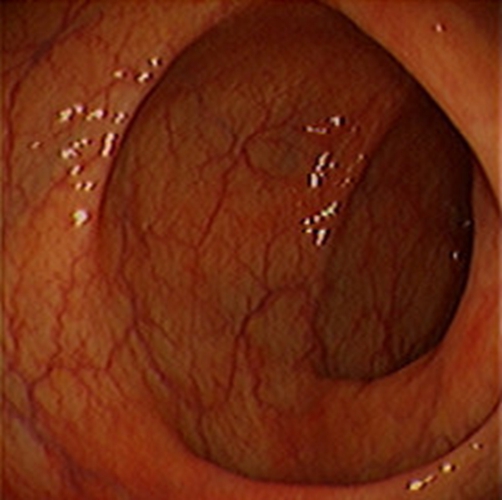

急性胃炎

急性胃炎胃部

急性胃炎相關文章